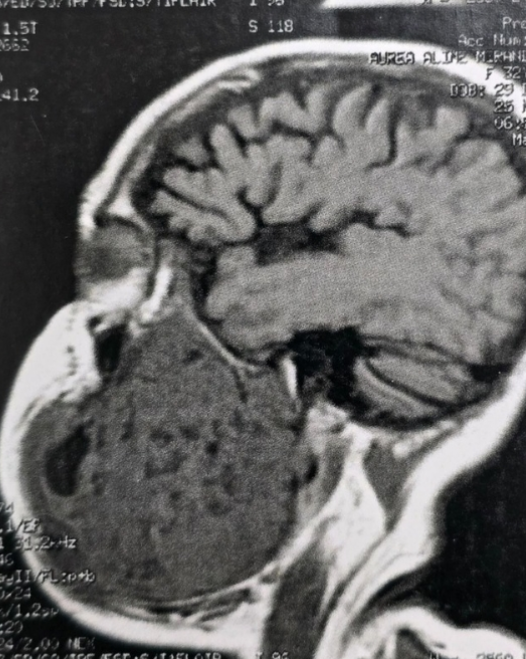

A paciente, natural do estado do Pará, convivia há oito anos com um ameloblastoma agressivo, que comprometia cerca de 50% da sua mandíbula esquerda. Essa condição não apenas causava uma severa deformidade facial, mas também dificultava a fala e a alimentação, resultando na perda de 30 quilos nos meses que antecederam a intervenção.

A equipe multidisciplinar que realizou a cirurgia foi composta por especialistas em bucomaxilofacial, microcirurgia de cabeça e pescoço e cirurgia plástica. O cirurgião Flávio Fayad explicou que o planejamento do procedimento demandou meses de estudos clínicos e exames detalhados. “Foi uma cirurgia complexa, mas conduzida com precisão. Realizamos a remoção completa do tumor, implantamos uma placa de reconstrução mandibular e utilizamos parte do osso da perna, por meio de um enxerto de fíbula vascularizada, para reconstruir a mandíbula”, detalhou.